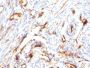

HL-60 or HeLa cells. Melanomas and Lymphoma. Carcinoma of Stomach, Cervix, Endometrial, Kidney or Colon.

Flow, intracellular (verified)|IF (verified)|IHC, FFPE (verified)|WB (verified)

Higher concentration may be required for direct detection using primary antibody conjugates than for indirect detection with secondary antibody|Immunofluorescence: 0.5-1 ug/mL|Immunohistology formalin-fixed 0.5-1 ug/mL|Staining of formalin-fixed tissues requires boiling tissue sections in 10 mM citrate buffer, pH 6.0, for 10-20 min followed by cooling at RT for 20 minutes|Flow Cytometry 0.5-1 ug/million cells/0.1 mL|Optimal dilution for a specific application should be determined by user